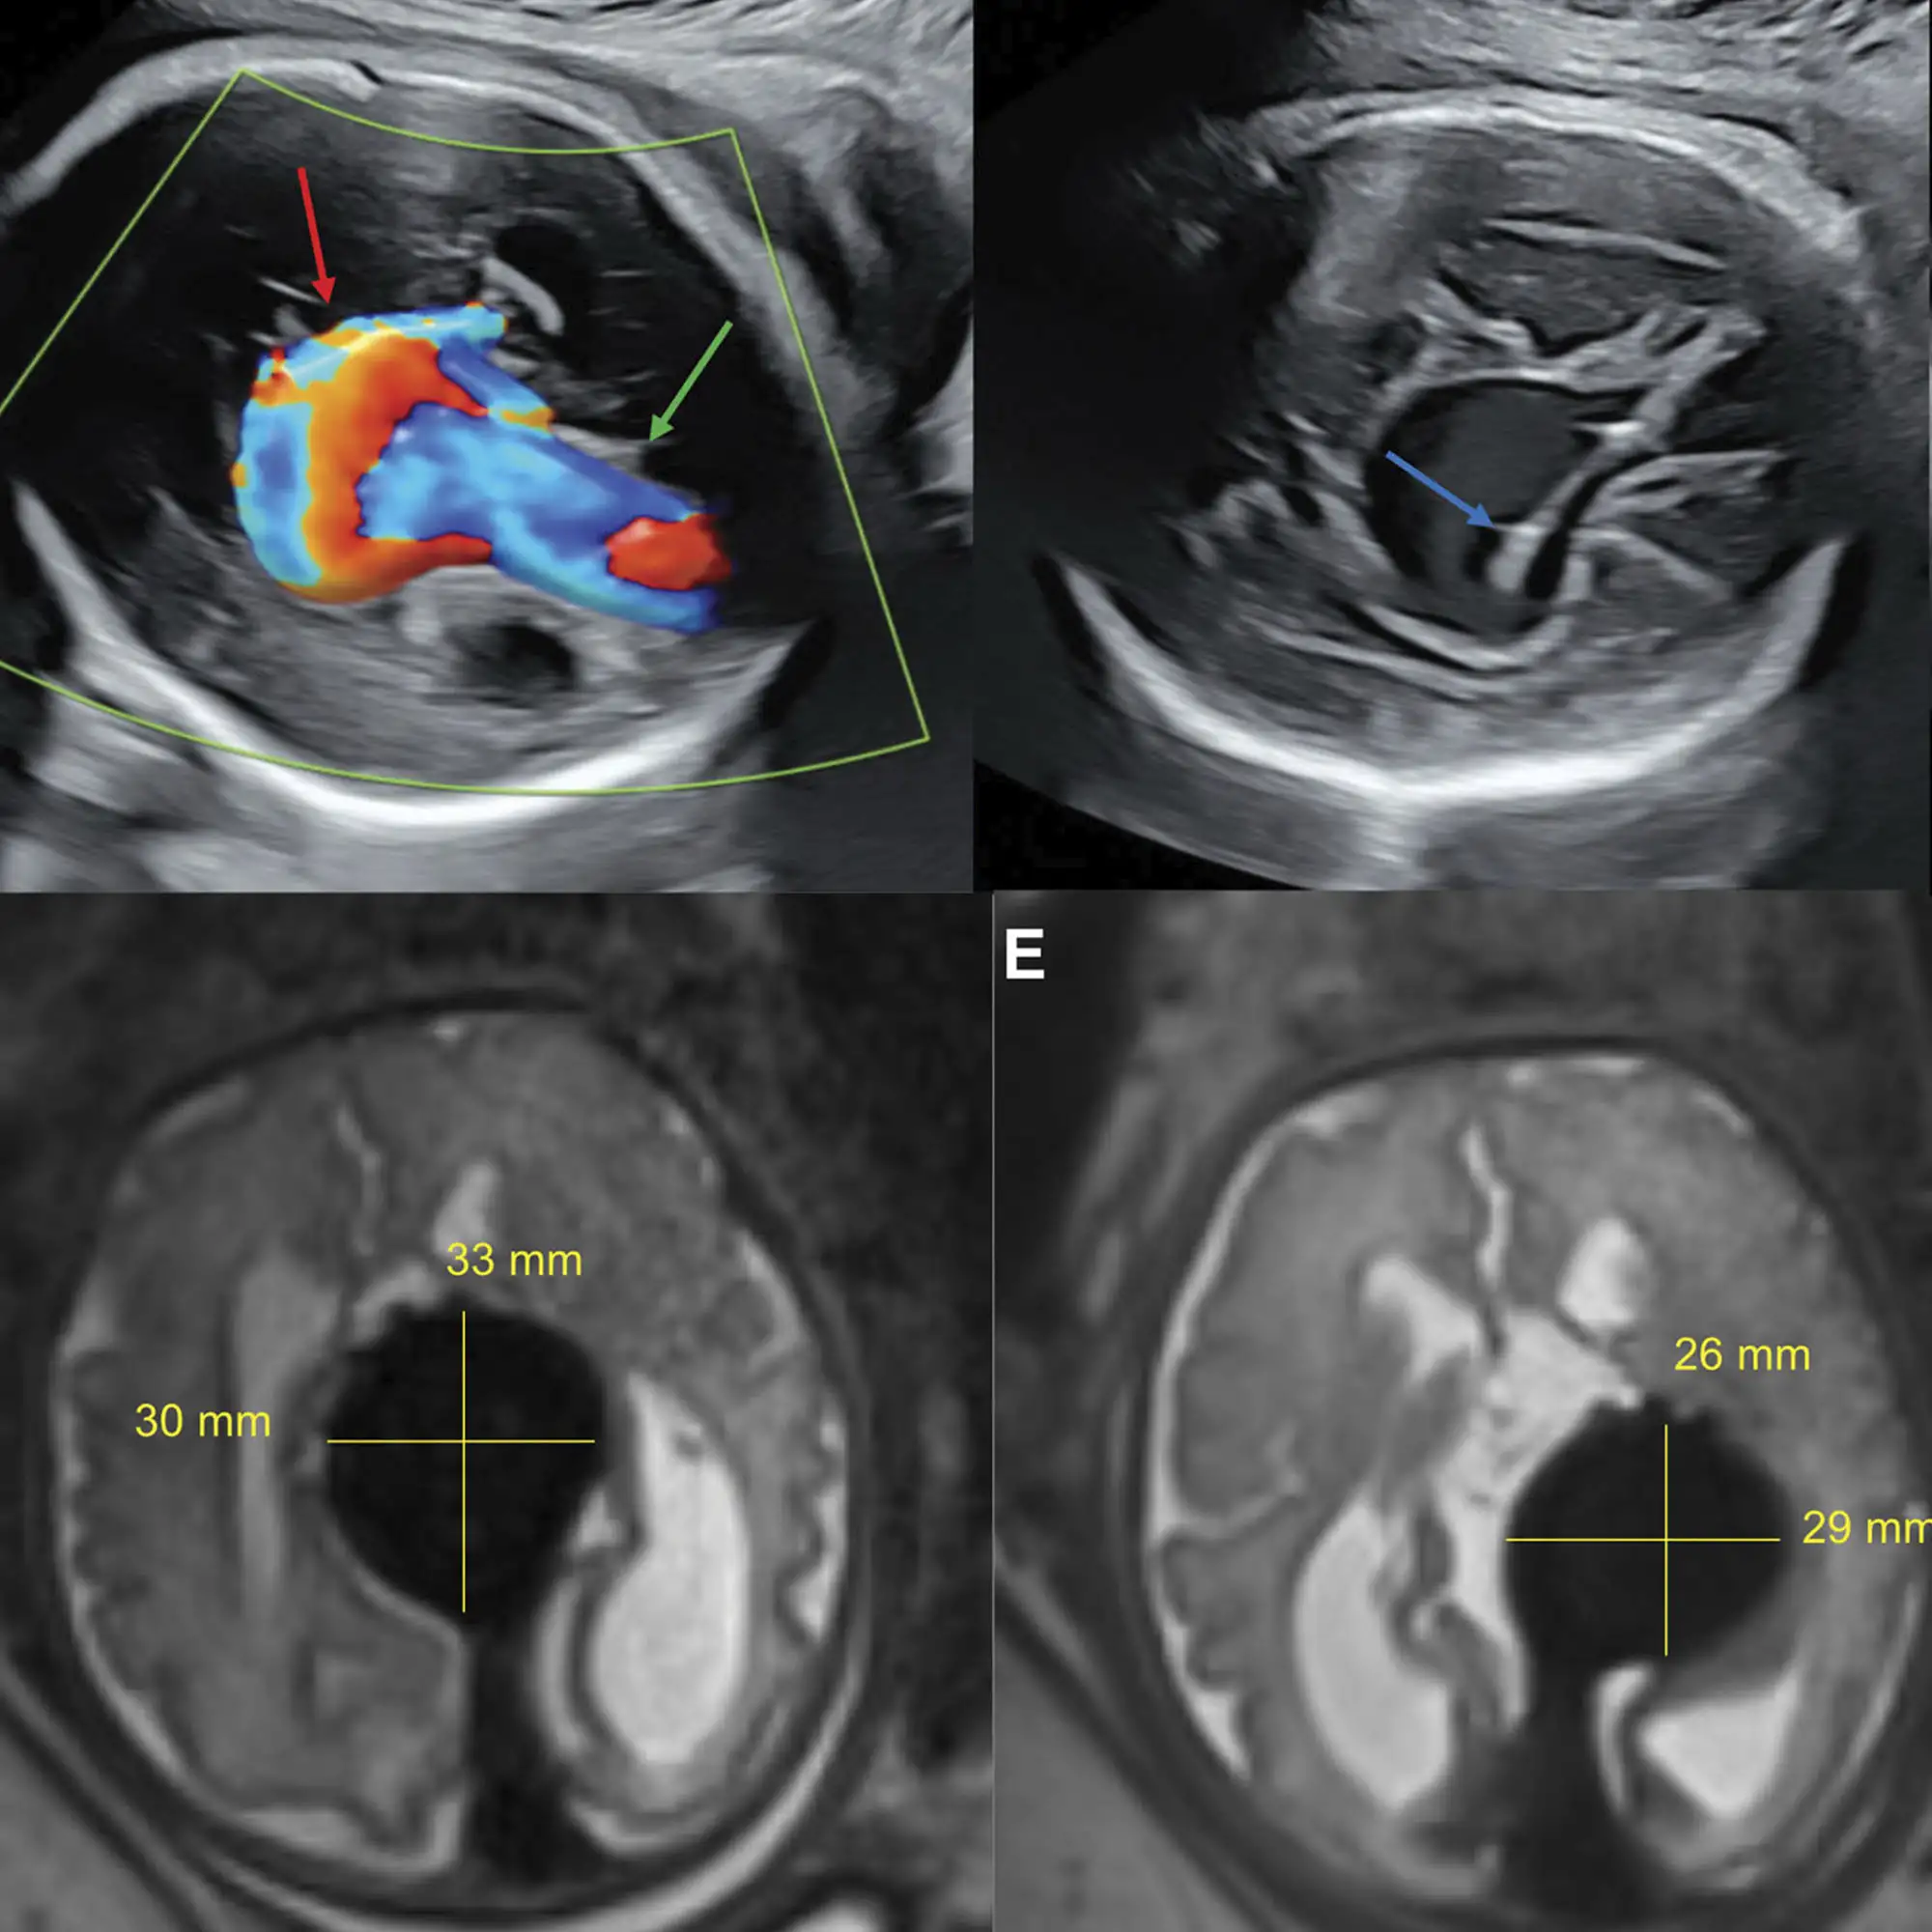

Вмешательство проводили в связи с артериовенозной мальформацией вены Галена (АВМ) у плода. В качестве методики была выбрана чрезматочная транскраниальная эмболизация под ультразвуковым контролем.

Оперативному вмешательству подверглась женщина с гестационным сроком 34 недели. Методика заключалась в проведении иглы в приводящую вену АВМ под контролем УЗИ и эндоваскулярную эмболизацию.